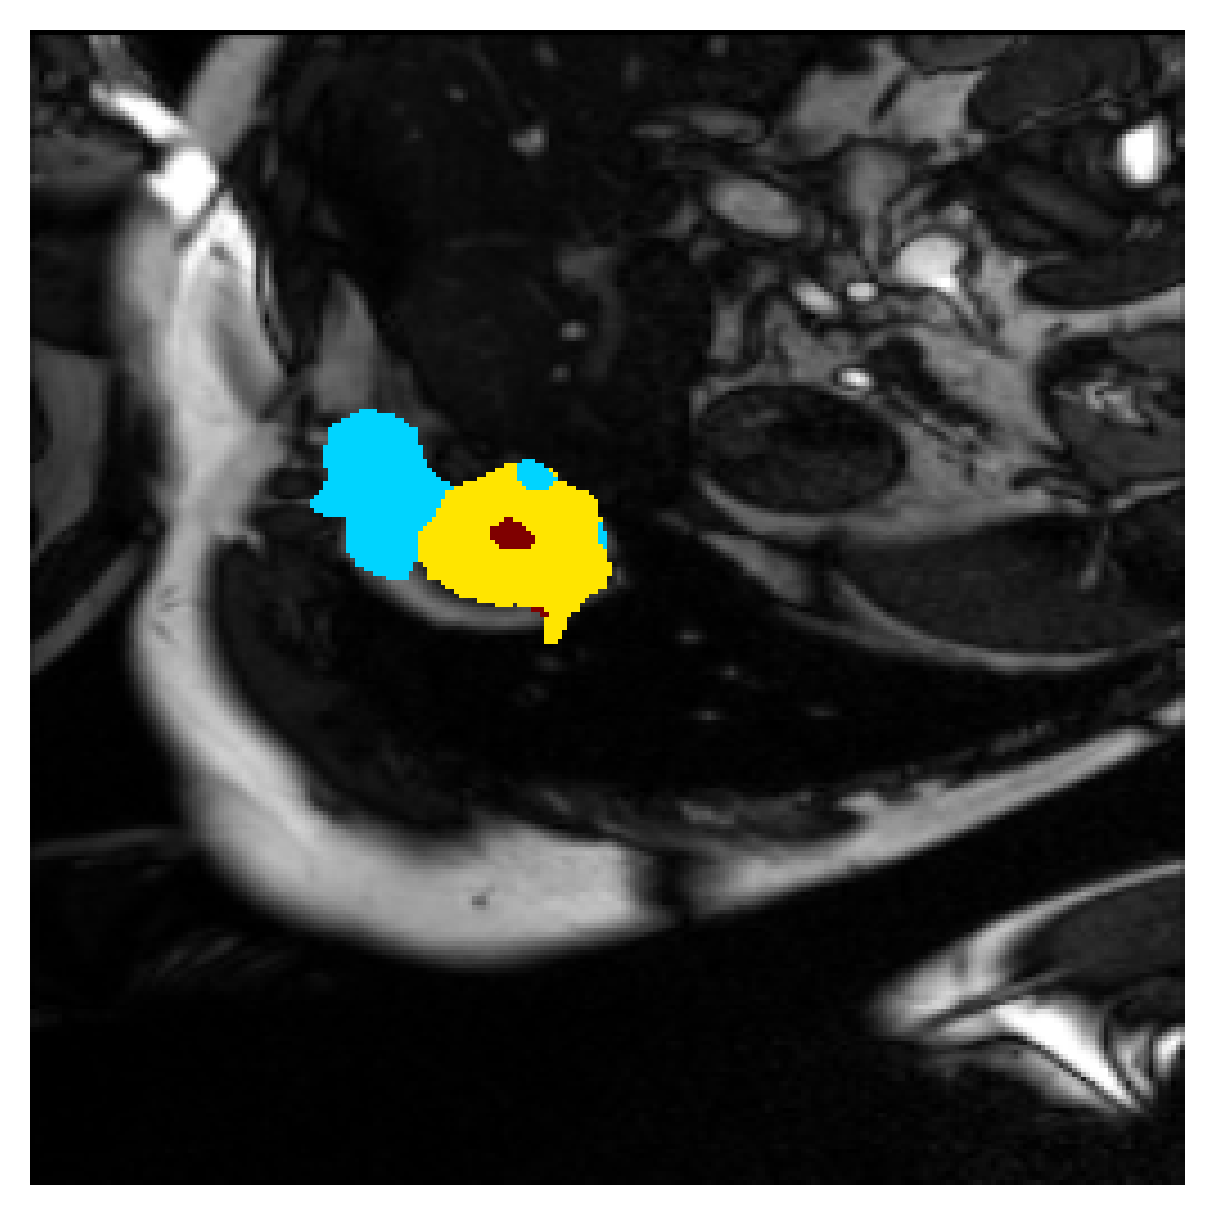

Qualitative comparison

| (a) Ground truth | (b) , full | (c) , weak | (d) |

| (full) | supervision | supervision | |

| (e) | (f) | (g) | (h) CRF-loss |

In Figure 6 we provide qualitative results on a number of randomly chosen test set slices. Upon visual inspection, we can observe that training with the intensity-aware distances (particularly with and ) follows the image gradients better and is better at recovering the underlying shape than the Euclidean version. The CRF-loss seems to recover the shape of the myocardium and left ventricle to some extent, but fails entirely on the right ventricle.